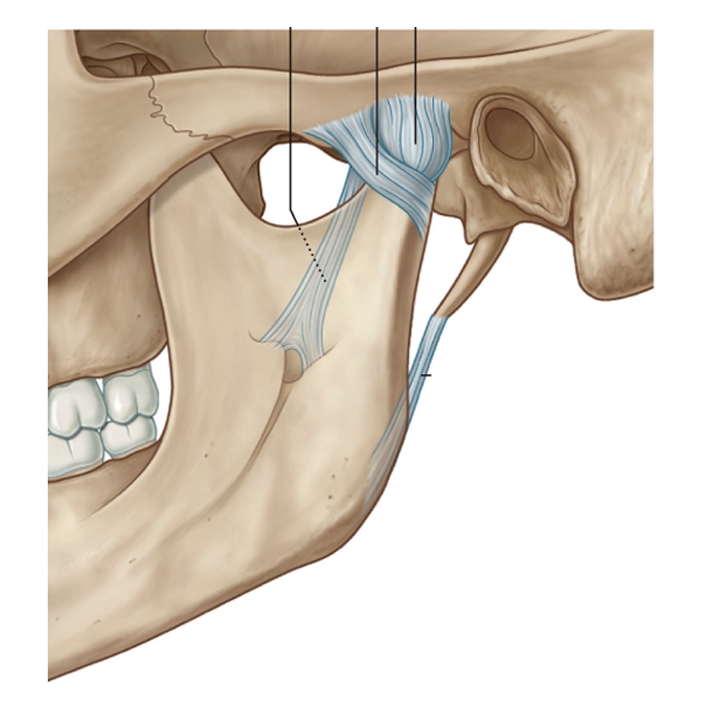

- Ver expedienteDisfuncion temporomandibular